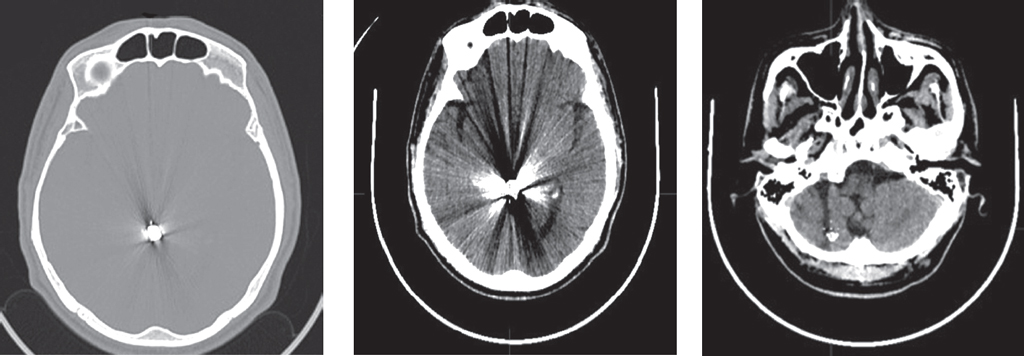

Fig. 1. Patient L. MRI of the brain — on coronal (а) and axial sections (б) (FLAIR mode) the area of contusion in the subcortical-cortical area of the left parietal lobe measuring up to 14 × 6 × 9 mm. Before the MRI, the patient had been treated for 6 days with a diagnosis of traumatic brain injury — brain commotion. According to CT of the head on the 3rd day after the injury, no structural disorders were detected

Рис. 1. Пациент Л. МРТ головного мозга — на корональном (а) и аксиальном срезах (б) (режим FLAIR) картина участка контузионных изменений в субкортикально-кортикальных отделах левой теменной доли размерами до 14 × 6 × 9 мм. До проведения МРТ пациент в течение 6 дней проходил лечение с диагнозом ЗЧМТ, СГМ. По данным КТ головы на 3-й день после травмы структурных нарушений выявлено не было